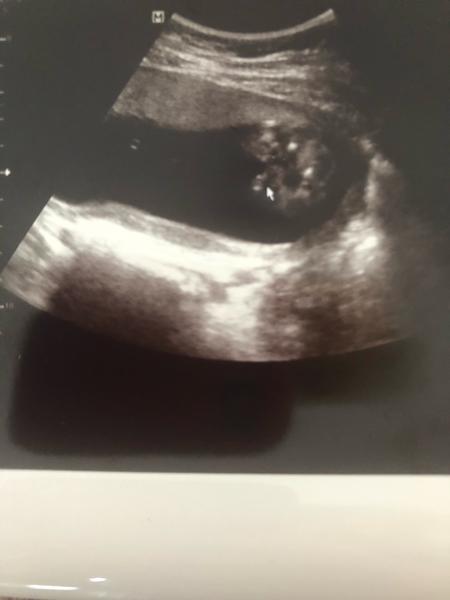

@odeta07 Nene, tohle je zadek z podhledu v 18 tt. Ta sipka ukazuje na pindu. 😆

@bublee Jo, tady je naše fotka z UTZ (screenshot z videa, kvalita nic moc, ale na videu aspoň mohl člověk velmi dobře zkoumat, fotky bývají někdy zavádějící)... všichni včetně mě tipovali kluka (manžel holku, ale UTZ pořádně neviděl, on to měl pocitově)... všichni říkali "vždyť tam jsou kulky jako blázen, jasnej kluk!"... a ona holka a kávové zrno 🙂

Já u tebe nevím, ona to holka klidně být může, víc by byl ten pytlík dole u zadečku, kdyby to byl kluk myslím... těžko říci...